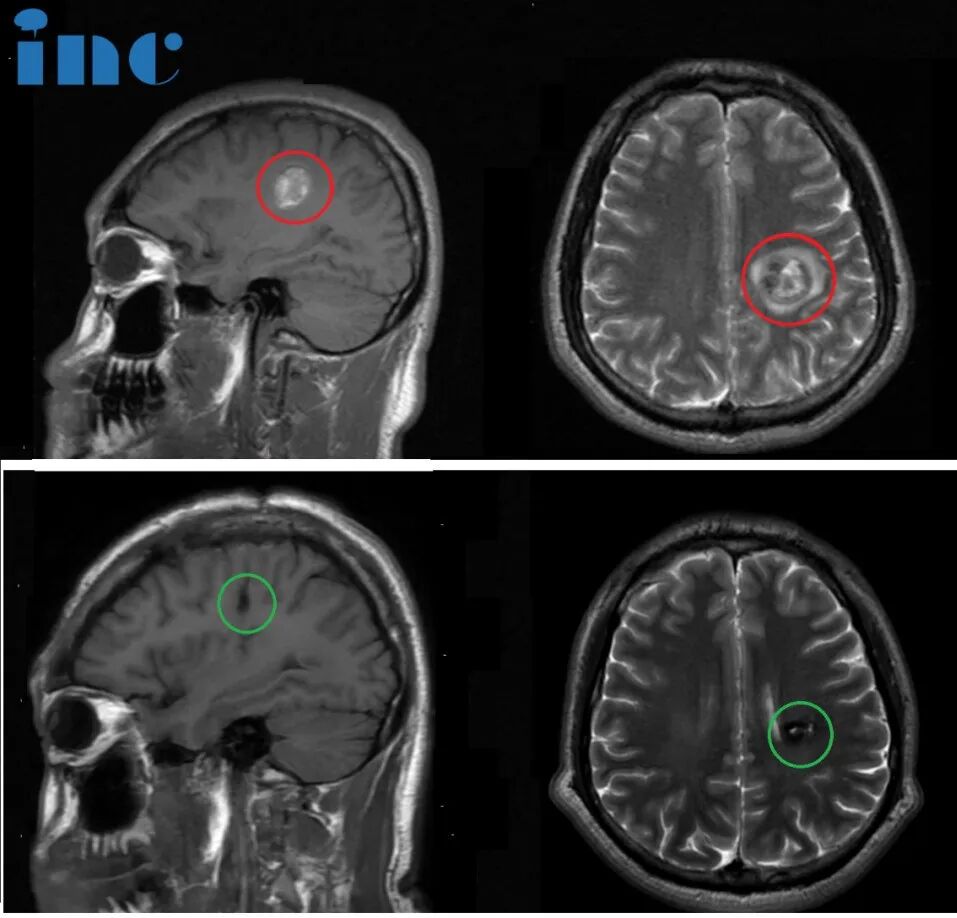

简要病史:23岁的彦文一年前感觉右手无力,写不了字,5月份就医检查左半卵圆中心海绵状血管瘤,住院治疗一周,期间右腿、右脚无力,走路不利索,医院给予保守治疗后出院。彦文父母一直苦苦寻求能为年轻的孩子顺利手术的主刀医生。今年4月,他们看到了国际神外教授巴教授来华示范手术消息,于是奔赴苏州寻求教授为孩子主刀手术。

治疗过程:4月9日,在苏州独墅湖医院,巴教授已经顺利为彦文顺利完成手术,全切左半卵圆中心海绵状血管瘤。

47岁女性,半卵圆中心海绵状血管瘤

简要病史:47岁的邓女士事业如日中天,对于工作,有着较强的责任心及较高的自我要求。一次定期体检却发现右脑额叶深部占位,大小约8mm,医生判断是海绵状血管瘤。咨询了上海的专家,但是医生的解释让他害怕,不建议手术,因为病灶部位太深,靠近功能区,手术风险大。而且目前病灶体积小,建议每年复查随访。查出海绵状血管瘤之后,邓女士发现有时工作太累了会头疼,近期还出现 6~7次无预兆性突然出现眼前漂浮物的现象,很快自行缓解。

治疗过程:2024年3月28日,巴教授中国行期间,一场疑难功能区海绵状血管瘤示范手术,成功拯救了47岁的邓女士于病魔的阴影之中。“I believe you, it’s a very (我很信任您,这是一个)就是正确的选择。”术后2小时,麻醉刚清醒,47岁的邓女士激动地用英语说出自己的术后感受,重新露出了大大的笑脸。